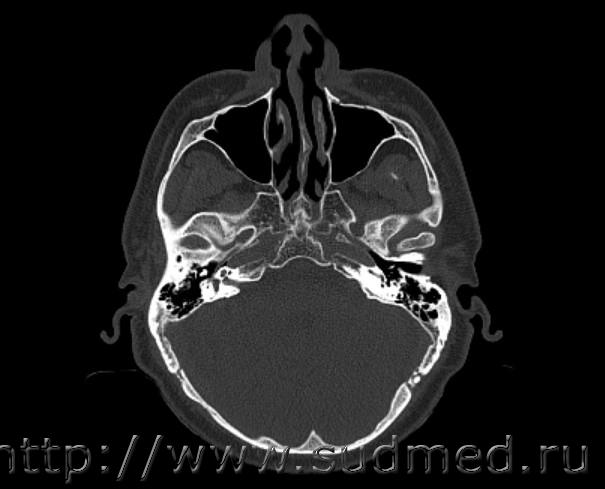

Уважаемые судмедэксперты, прошу вас помочь в одном вопросе. Получил травму, попал в больницу, сделали КТ, нашли перелом позвоночника. После выписки у меня сильно болело лицо (левая часть),наблюдалось онемение левой части зубов верхней челюсти), гематома проходила долго, болезненные прикосновения. В поликлинике сказали что все пройдет со временем. Обратился в больницу за КТ, но там уже все затерли. Пришлось спустя 3 месяца после травмы делать новое КТ.

На КТ я увидел (как мне показалось) двойной перелом передней стенки левой верхнечелюстной пазухи с деформацией передней стенки. Однако судебно-медицинская экспертиза не выявила данной паталогии. Типа это отверстия под нервы, а не перелом, слышал что-то вроде этого.

Вопрос, был перелом с вдавливанием передней стенки или перелома нет?

По одному скану, выполненному через 3 месяца после травмы, сложно судить о наличии или отсутствии перелома передней стенки верхнечелюстной пазухи. Возможно, что одна линия перелома была (второе завуалированное просветление идентично таковому на противоположной стороне). Верхнечелюстные пазухи с обеих сторон без признаков отека и/или без уровней жидкости. После перелома такое может быть, но, несколько более ожидаем хотя бы минимальный отек в полости пазухи, стенка которой была сломана.

В больнице затерли первичную КТ, сначала сказали что вирусы почикали в результате компьютерного сбоя а потом что стерли в связи с необходимостью освобождения жесткого диска. Похоже на то что они просто скрывают что незаметили перелом пазухи. Версии сомнительные. Поэтому есть только это КТ, сделанное через 3 месяца. Обращался к судмедэксперту, он написал "возможно перелом пазухи но судить с уверенностью невозможно. На видео наблюдается на 3 снимках, шаг - 1 мм., т.е. трещина длинной 3 мм - первая, вторая - 2 мм.